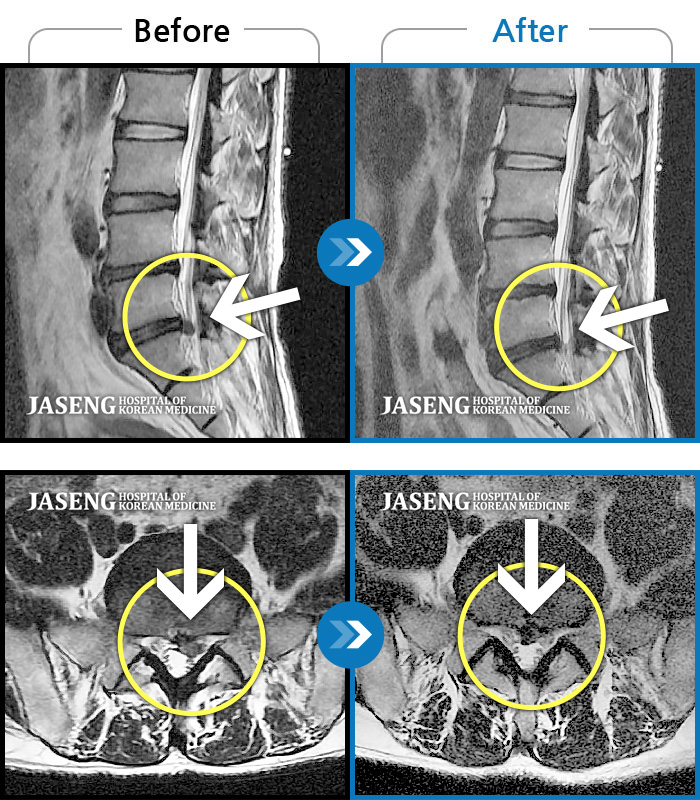

MRI 치료사례